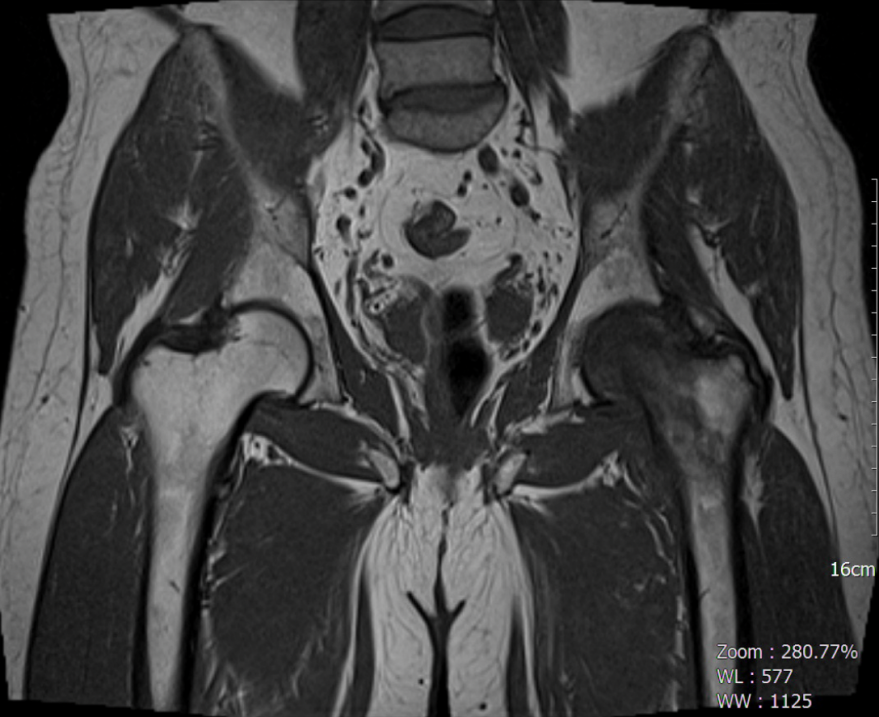

MRI显示股骨头和颈部出现严重的髓样水肿,左髋关节有叶状积液,还有一个小小的松散体(图1,2)。没有创伤史的患者被认为是TOH。

图2;T1涡轮自旋回波(TSE)冠状位MRI